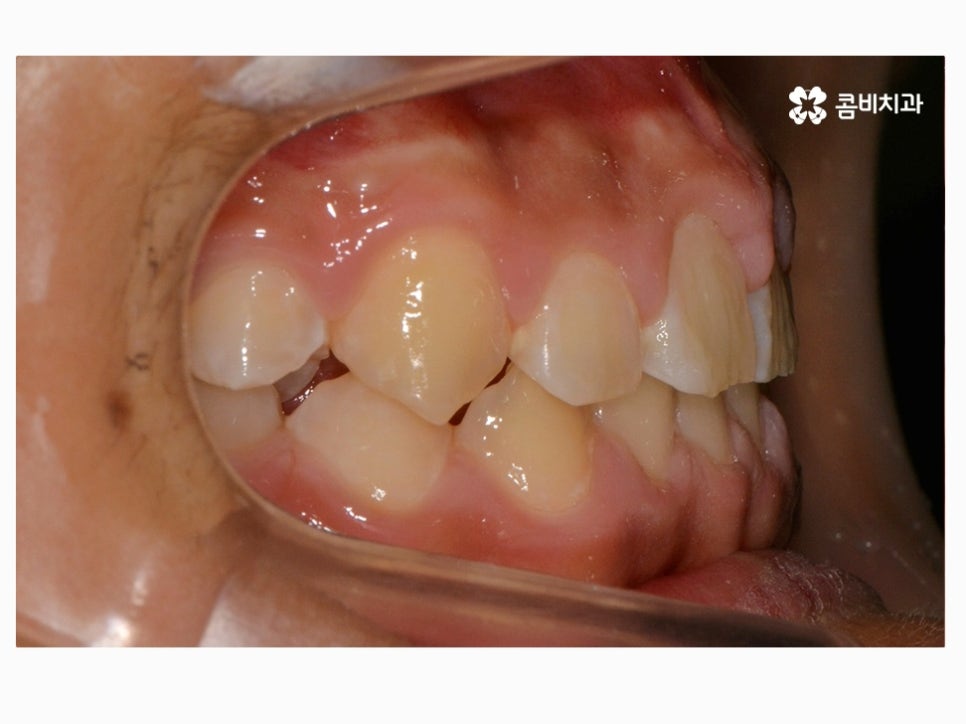

과개교합은 부정교합의 종류 중 하나라고 할 수 있으며

윗니가 아랫니를 정상보다 많이 덮고 있는 형태로 흔히 과개교합 혹은

피개교합으로도 불리고 있어요.

보통 윗니가 과도하게 돌출되어 있거나 치아의 크기가 큰 경우,

아랫니가 과하게 안쪽으로 들어가 있는 경우, 선천적으로 골격성 부정교합에

해당되거나, 이갈이 등 어금니에 과하게 힘이 가해지면서

마모되거나 치관의 길이가 짧아진 경우에

윗니가 아랫니를 덮고 있는 형태를 하게 될 수 있는데요.

부정교합을 치료하는 방법은 나이대와 어떤 상태인지 진단에

따라서 달라질 수 있는데 위 케이스처럼 일반적인 치아교정으로

진행이 되는 경우도 있고 구외 교정 장치를 활용하는 경우 등 진단에 따라 다양할 수 있어요.